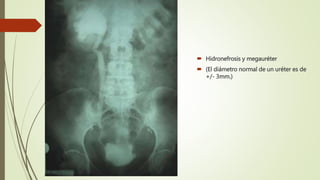

 Hidronefrosis y megauréter

 (El diámetro normal de un uréter es de

+/- 3mm.)

 Hidronefrosis ymegauréter  (El diámetro normal de un uréter es de +/- 3mm.)